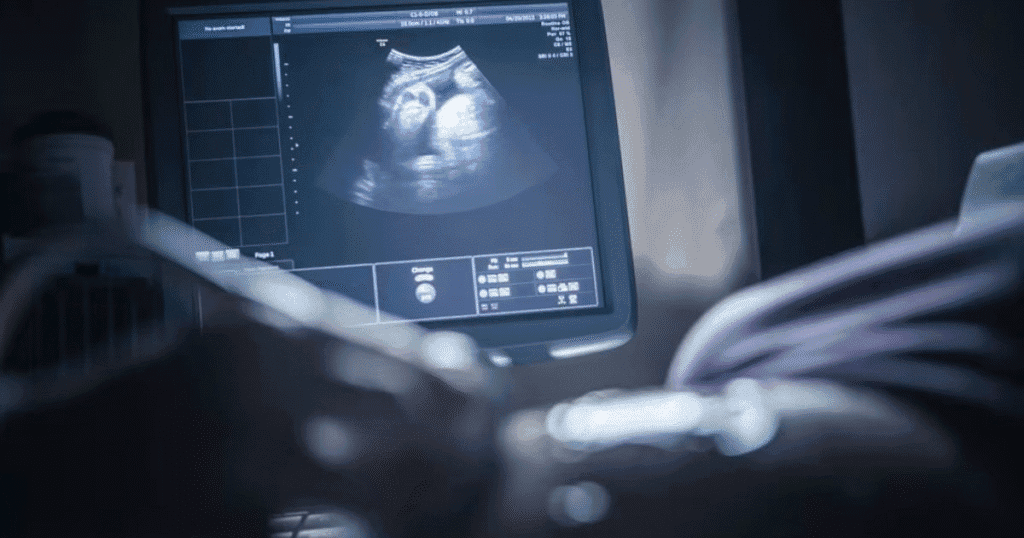

An ultrasound tech, or diagnostic medical sonographer, operates the imaging machine. They capture images of the body’s organs and tissues. Doctors can use these images to spot and check their patients’ medical conditions.

Ultrasound tech can be found in hospitals where they sometimes do emergency scans along with the radiologist. Ultra sound techs are also available at clinics and private practices in small towns. Furthermore, they can be found at OB/GYN and cardiology specialty centers.